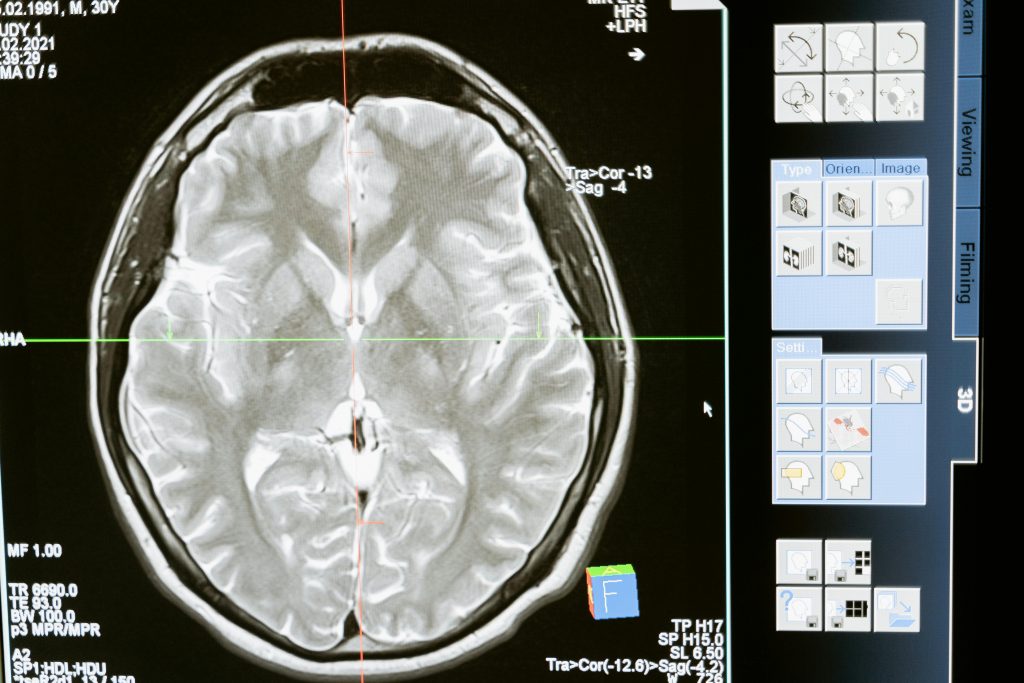

You’ve likely heard people call MRI scans “safe because there’s no radiation.” But recently, conversations online have raised new questions — can strong magnetic fields in MRI scanners actually affect our DNA? And what happens if you undergo a whole-body MRI every couple of years for health monitoring?

At London Osteoporosis Clinic, we’re passionate about providing evidence-based clarity for patients navigating preventive health choices. This article explores what decades of research say about MRI’s biological safety, what small studies have found regarding potential cellular effects, and why a 1.5–3 Tesla whole-body MRI every two years remains within globally recognised safety standards.

If you’re considering a whole-body MRI as part of a YouOptimised™ or BoneRevive® health assessment, this guide explains what’s really happening inside your body during the scan — and why, when used responsibly, MRI is one of the safest diagnostic tools in modern medicine.